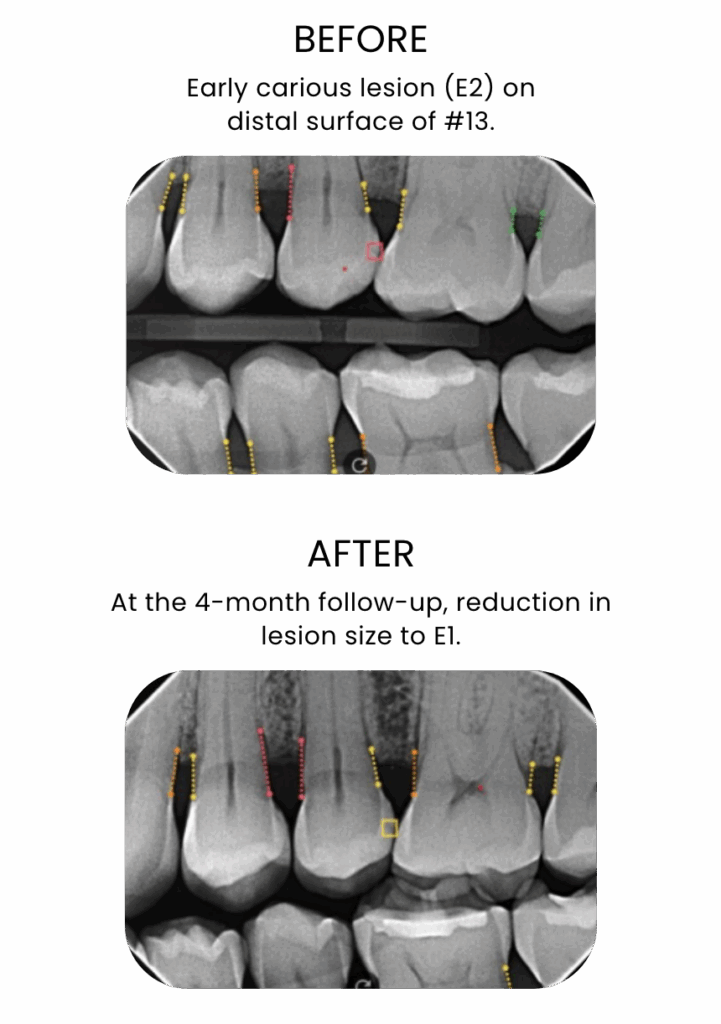

Interproximal early carious lesion interpreted with AI

50-year-old male patient

Courtesy: Dr. Rebecca Pounds

Scientific and real-world evidence has demonstrated that one application of Curodont Repair Fluoride Plus is sufficient to treat one lesion, with a success rate of over 90%. (Shaalan O et al. Clin Oral Investig. 2024;28:438)

Success with Curodont Repair Fluoride Plus is seen as the stopping of the progression of the treated lesion and the restoration of mineral density throughout the depth of the lesion, with studies showing a success rate of over 90%.(Shaalan O et al. Clin Oral Investig. 2024;28:438)

A recent study demonstrated that Curodont Repair Fluoride Plus led to a significant increase in mineral density throughout the lesion depth within only 2 weeks using Micro-CT and Scanning Electron Microscope analysis. [Cowen M et al. Biomater Res Rep 2025 Aug;175 Curodont™ Repair Fluoride Plus – Dental Advisor (Accessed 04/28/2026)]

Due to the limitations of currently available diagnostic technologies in clinics, such as x-rays, the improved mineral density may not be immediately visible on x-rays.